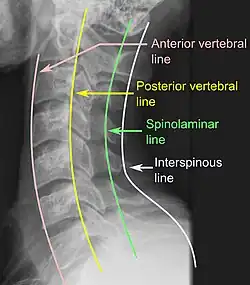

CT scan or X-ray images are evaluated for the presence or absence of directly visible fractures. In addition, indirect signs of injury by the vertebral column are incongruities of the vertebral lines,[11] and/or increased thickness of the prevertebral space:[12]

X-ray of normal congruous vertebral lines

X-ray of normal congruous vertebral lines -

![CT scan of normal congruous vertebral lines.[11]](./_assets_/Vertebral_lines.png)